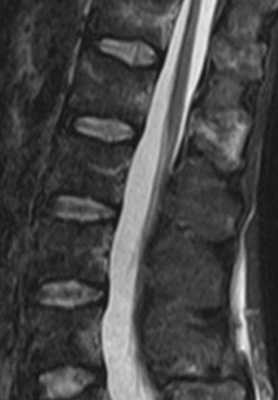

МРТ позвоночника. Т1-взвешенная сагиттальная МРТ грудного отдела. Жировая дегенерация костного мозга после лучевой терапии.